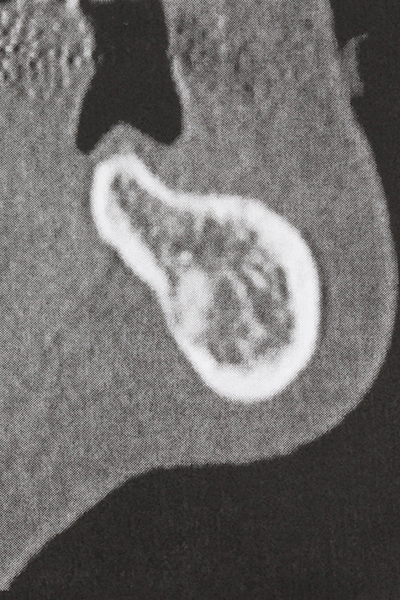

Когато се извършват хирургични процедури върху кост в непосредствена близост до чувствителни структури като кръвоносни съдове или нерви, ротиращите инструменти създават значителен риск за ятрогенно нараняване. Пиезоелектрическите апарати могат да бъдат от помощ при препарация на костно покритие и отстраняване на твърда кост близо до нерви, особено за оголване на нервите след ятрогенно нараняване, както и по време на латерализация на нервите за резекционни и реконструктивни процедури или поставяне на имплант (Фиг. 17-20). Лекият контакт между пиезонакрайника и нерва по принцип не води до нараняване, но ако действате непредпазливо с трионообразни движения или приставки за остатъчен костен субстрат, може да причините временно или перманентно увреждане на нерва. Въпреки това, рискът от увреждане се счита за много по-малък, отколкото при употреба на триони или ротиращи инструменти (Pereira, Gealh et al. 2014).